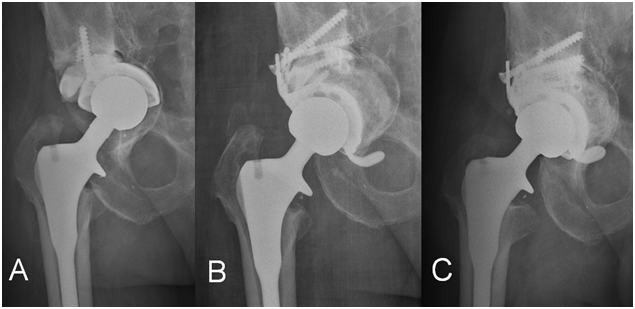

The bone defect caused by the arthritic process can be addressed using bone autograft from the own removed femoral head. This is the case for hip dysplasia or for rapid progressive osteoarthritis. For Crowe type II and III hips, the placement an autogenous superior lateral bone augmentation, has provided satisfactory results.1 This technique allows restoring the biomechanical normal position of the center of rotation of the hip and increases bone stock, being this an advantage for an eventual future revision. According to Gerber and Harris2 and Mulroy and Harris,3 autogenous grafting had a high risk of collapse at the long term follow-up. Although all the grafts united initially, resorption occurred by late revascularization and creeping substitution. In these series, the acetabular rate of failure was 21% after seven years and 46% after 12. More favorable series show a successful reconstruction such as 93,9% at 8,3 years4 or 94% at 10 years.5 In order to avoid failure, it has been stated that the most important factor fur success is to restore the anatomical center of rotation of the hip.6 Another option is to restore the center of rotation and to obtain coverage using a metal supplement. We are increasingly using this option in our practice and recently published our results, by using Trabecular Titanium™ (TT) cups in selected primary total hip arthroplasty cases. The advantage is the simplification and reproducibility of the surgical procedure, the enhanced stability that it provides, and in the long term to prevent collapse. The inconvenient, being the same in the revision setting, would come from the difficulty of handling with this piece of metal in a possible future revision: the removal, if needed, could provoke a worse bone defect. But also, due to the modularity, in some cases this piece could be retained to aid for the reconstruction (Figure 1). Future studies have to compare the results of the use of allograft versus highly porous metal augments for primary cases with acetabular bone defects.

Figure 1A Image depicting a cup loosened with a Paprosky type 3B defect. In this case we trabecular titanium supplement was found to be stable and was kept in place, and we decided to add a bulk structural allograft with a  Delta TT cup (Lima Corporate) with flanges.

Figure 1B The evolution was satisfactory and shown in the postoperative images.

Figure 1C One year follow-up.